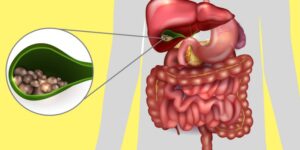

A grande maioria de Câncer Colorretal se formam nas glândulas produtoras de muco (adenocarinomas) dentro do cólon ou reto e se desenvolvem ao longo de vários anos. Geralmente, eles começam como pequenos grupos de células benignas (não cancerosas) no cólon conhecido como pólipos.

Ao mostrar alguns sintomas, os pólipos podem eventualmente tornar-se cancerosos. É principalmente por essa razão que os médicos recomendam exames regulares para encontrar pólipos antes de se tornarem cancerosos.

Forma das Fezes: Preste atenção a qualquer alteração na forma das fezes, principalmente se elas estiverem subitamente mais finas, pode ser um dos Principais Sintomas de Câncer Colorretal. Isso poderia ocorrer, pois a presença de pólipos faz com que o intestino se estreite e não permita a evacuação normal das fezes.